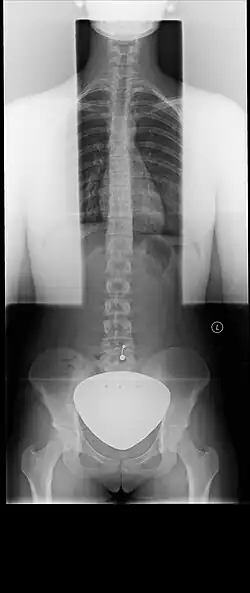

Starting in the 1950s, lead shielding began to be used on patients during all X-rays over the abdomen to protect the gonads (reproductive organs) or a fetus if the patient was pregnant. Dental X-rays would also typically additionally use lead shielding to protect the thyroid. However, a consensus was reached between 2019[4][5][3] and 2021[6][7] that lead shielding for routine diagnostic X-rays is not necessary and may in some cases be harmful. In part, this is due to improved understanding of the effects of radiation on patients, as the amount of radiation patients were exposed to in routine X-rays and CT scans was found to not affect fertility or a developing pregnancy. It was also due to the improvement of X-ray machines. For instance, older X-ray machines would use a set amount of radiation, and used film which requires more X-rays.[3] Modern X-ray machines are digital, and automatically use the minimum amount of radiation needed to image the patient, which means overall the radiation levels are much lower than in the past; however, if the lead shield is in the field being imaged, the machine will produce more X-rays in order to attempt to penetrate the lead shield. Additionally, if the shield is in the field, this may affect the image produced, requiring a second X-ray to be performed, which would also lead to overall increased radiation exposure. Additionally, patient shielding is ineffective at reducing internal scatter; because only a portion of the patient is shielded, X-rays may still go through the gonads or fetus from bouncing off the imaged areas internally.[8]